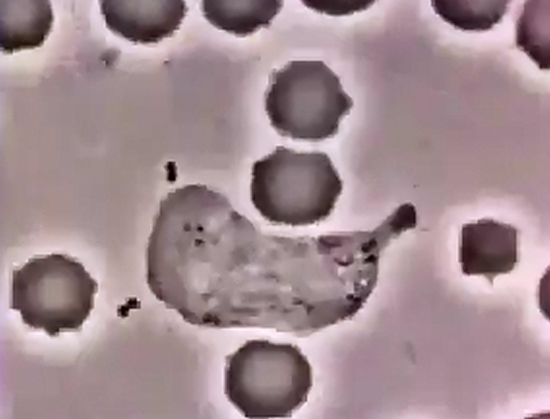

Lökasitin Bakteri Kovalaması